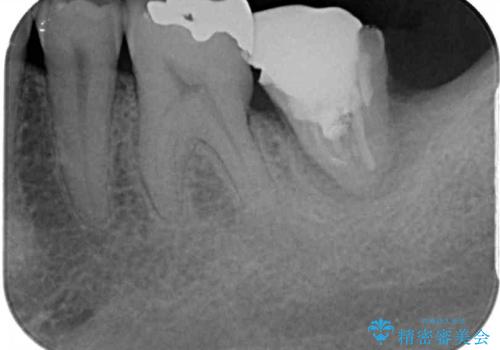

上顎の奥歯は、左右ともに外側に転位しており、特に右上はむし歯の範囲が広く、根管治療も必要な状態でした。

左下の奥歯は状態が非常に悪く、保存は困難と判断されたため、インプラントによる補綴治療が必要でした。